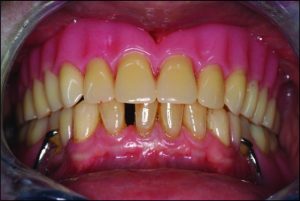

Occlusal discrepancies negatively affect the success of the prosthesis. In partially edentulous cases, due to reasons such as loss of teeth at different times or prolonged edentulism, the remaining teeth tend to tip, drift, or supra-erupt into the edentulous spaces (Figure 9-6).

Figure 9-6. In a patient who has been edentulous for a long time, positional changes in the natural teeth lead to occlusal discrepancies.